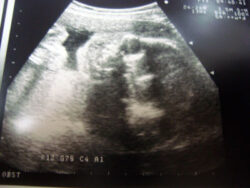

拳を握りそれぞれの指を一本づつまっすぐ立てる。すると中指だけがまっすぐに ならない。なぜだろうか? 誰か教えて下さい・・。 さて・・今日は、私は仕事が休み。 それに合わせ、お腹の中の我が子の検診がありました。 朝7時頃起 […] 続きを読む »

日々、のっちょのお腹の中では、我が子が元気に動いてます。 『当たり前ですが、絶対に子は親を殴るなんて事があってはいけません』。 でもね、親を殴っていい時期なんてないけど、その暴力が必要な時期があるんです。 そう・・それが […] 続きを読む »